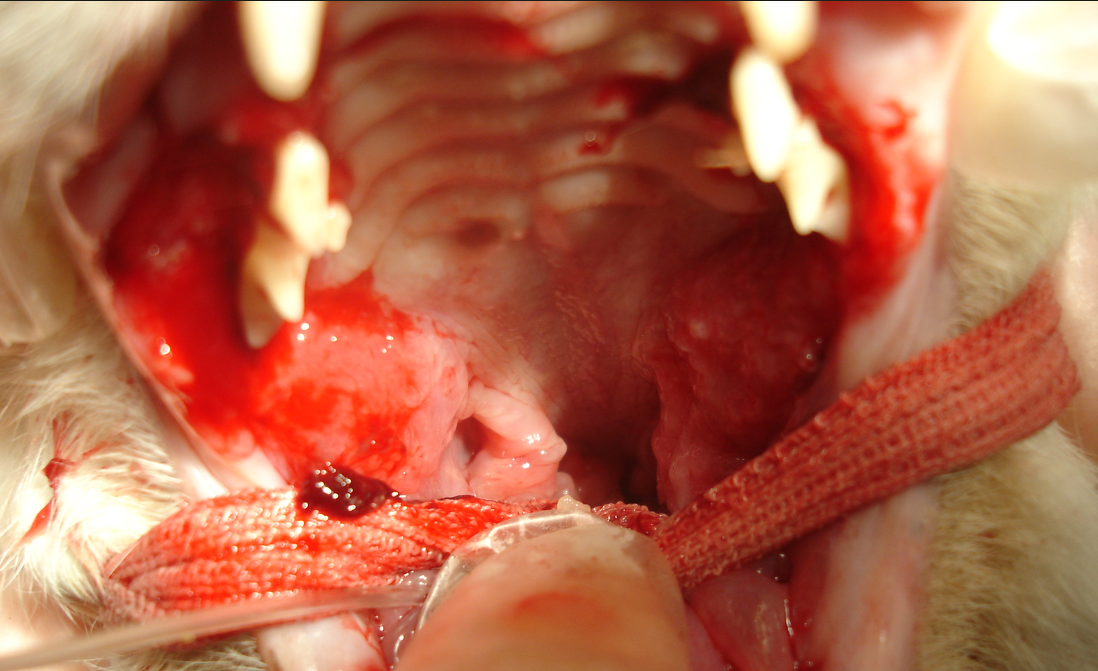

この子は猫エイズのため、口角の奥が左右両方とも大きく腫れ上がる口内炎を起こしています。

そしてこの子は歯肉全般が発赤して腫れるタイプの口内炎を起こしています。おそらく猫の歯牙疾患と呼ばれる体質が関連した口内炎と考えられました。どちらの子も初期は抗生物質や消炎剤での治療を行っていましたが、食欲に影響が出てきたため、荒療治ですが、犬歯以外の歯を抜歯することで炎症を抑えることに成功し、口内炎を鎮静化することができました。